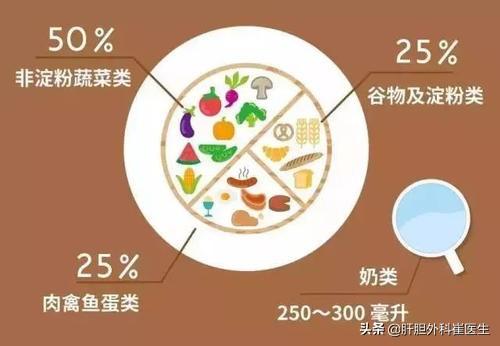

Si vous présentez une légère carence en potassium lorsque vous vous examinez et que vous ressentez occasionnellement les symptômes d'inconfort mentionnés ci-dessus, le Dr Wong vous propose quelques suggestions pour compléter votre apport en potassium par le biais de l'alimentation. Les bananes sont les plus riches en potassium, mais le nori, les épinards et les tomates sont également de bons choix. Un autre favori est le jus d'orange, un jus de fruit naturel riche en potassium.

Mais pour la plupart des habitants de lUn faible taux de potassium n'est pas très grave.Dans ce cas, le moyen le plus sûr et le plus efficace est de manger davantage.Aliments riches en potassiumCertains fruits et légumes contiennent des concentrations de potassium encore plus élevées, comme les bananes, les pommes, les pêches, les raisins, les poires, les pastèques, les épinards, les ignames, les fèves de soja, l'amarante et les oignons nouveaux.

solSelon les directives diététiques chinoises pour les résidents, nous devrions consommer au moins 2 000 mg de potassium par jour.Dans notre alimentation quotidienne, en effet, de nombreux aliments sont riches en potassium, compléter ce besoin quotidien n'est pas difficile, alors quels sont les aliments riches en potassium ? Monsieur vous les présente brièvement.

●légumineusesC'est une excellente source de potassium. Parmi les produits à base de soja, non seulement ils sont riches en potassium, mais ils sont également relativement riches en fibres alimentaires, avec environ 130 grammes de haricots blancs et peuvent apporter421 mg de potassiumLes lentilles sont également une bonne source de potassium.

●Pommes de terre et arachides. Six taels de pommes de terre fournissent1600 mgde potassium, une demi-livre d'arachides apporte1100 mgLe potassium, en plus des deux ingrédients, est tout aussi riche en fibres alimentaires, et une augmentation adéquate de la consommation de pommes de terre est également très importante pour maintenir la santé du tractus intestinal.

●Épinards, betteraves. Cent grammes de betterave rouge contiennent encore environTrois cents milligrammes de potassium.Les épinards sont également riches en potassium, en vitamine A, en vitamine K et en calcium. Leur teneur en calcium est relativement élevée, mais il est recommandé de les faire blanchir lorsqu'on les cuisine, car leur teneur en acide oxalique est relativement élevée.

●Tachanoko, jus d'orange. Une tasse d'environ une demi-livre de jus d'orange fournira près de500 mg de potassium.Les agrumes sont également riches en vitamine C, qui joue également un rôle important dans notre organisme, mais le Dr Xie vous conseille de ne pas consommer beaucoup de jus d'orange si vous avez un taux d'acide urique élevé, car vous risquez d'augmenter encore votre taux d'acide urique, surtout à long terme.

●bananesRiche en potassium, comme vous le savez certainement tous, une banane mûre contient près de 450 mg de potassium, mais si vous souffrez de diabète, ce n'est pas une bonne idée d'abuser des bananes en raison de leur teneur élevée en sucre.

Les aliments les plus riches en potassium sont les bananes, les épinards, les tomates et le chou violet, dont la teneur en potassium est également très élevée. En outre, nous mangeons souvent des oranges, qui sont des sortes de fruits riches en potassium, et les aliments ou les fruits peuvent servir de complément au potassium.

Deuxièmement, il convient de veiller à une alimentation équilibrée dans la vie quotidienne et à une supplémentation appropriée en fruits et légumes frais riches en potassium, tels que les bananes, qui contiennent 0,25 g de potassium pour 100 g de bananes. Les cuisseaux de poulet, les champignons portobello et d'autres champignons contiennent également des niveaux élevés de potassium, avec 4 g de potassium pour 100 g de cuisse de poulet et 3 g de potassium pour 100 g de champignons portobello ; en outre, les noix de coco, les oranges, les pommes de terre, les haricots de soja et les fèves sont également riches en potassium.